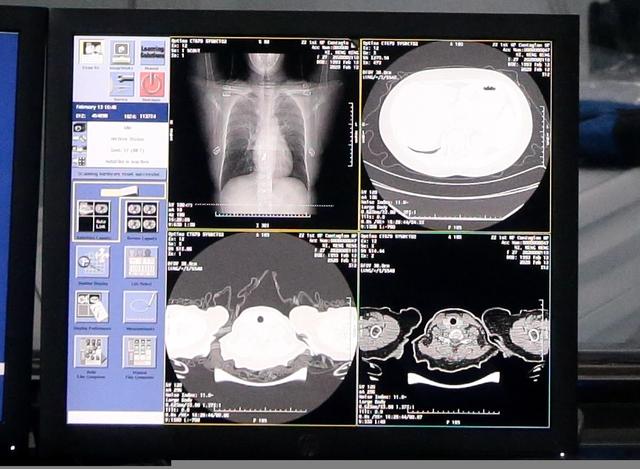

例如,达摩院AI突破了新冠肺炎样本数据不足的局限,训练了全新的AI算法模型,可在20秒内对新冠疑似患者CT影像做出判读,分析结果准确率达到96%,大幅提升临床诊断效率。技术率先在郑州小汤山投入使用。

此外,达摩院AI算法还应用于新冠肺炎的病原学检测上,与浙江省疾控中心合作,利用算法将疑似病例基因分析时间缩至半小时,同时可以避免核酸检测出现的漏检情况。

这些成果不仅得益于达摩院医疗AI团队多年的技术积累,云计算的优势也在这次算法研发与推广中体现了出来。有阿里云团队在背后支撑, AI团队研发出一版本算法只需要2天。